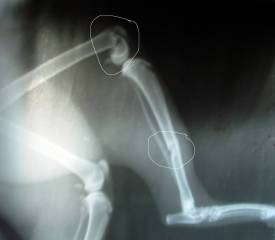

Как-то Мальчишке "ножку" сломали, кости собирали... резали, лечили... чинили...

потихоньку поправился, стал снова ловить […] -